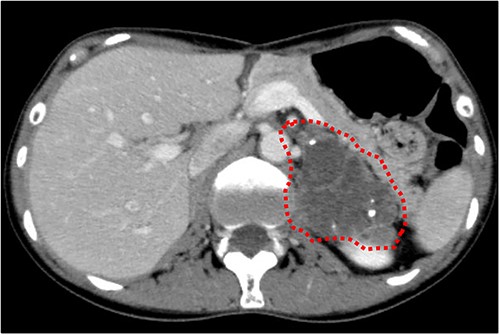

Cranial magnetic resonance imaging (MRI) showed two nearby ring-shaped enhanced tumours with maximum diameters of 3.3 and 2.4 cm in the left cerebellum (Fig. 3). Contrast-enhanced computed tomography (CT) revealed swelling of the left adrenal gland with a maximum diameter of 6 cm (Fig. 4). Positron emission tomography showed other high fluorine-18-deoxyglucose accumulations without the above lesions. The tumour markers, including CEA, CA19-9, and CA125, were within normal ranges. The cerebellar tumours were resected and diagnosed because the patient had neurological symptoms. Histopathological findings of the resected specimens indicated signet-ring cell carcinoma (Fig. 5), which was diagnosed as metastatic gastric cancer. Resection of intracranial tumours rapidly improved her neurological disturbances.

Abdominal CT findings. A calcified tumour with a maximum diameter of 6.0 cm was observed in the left adrenal gland.